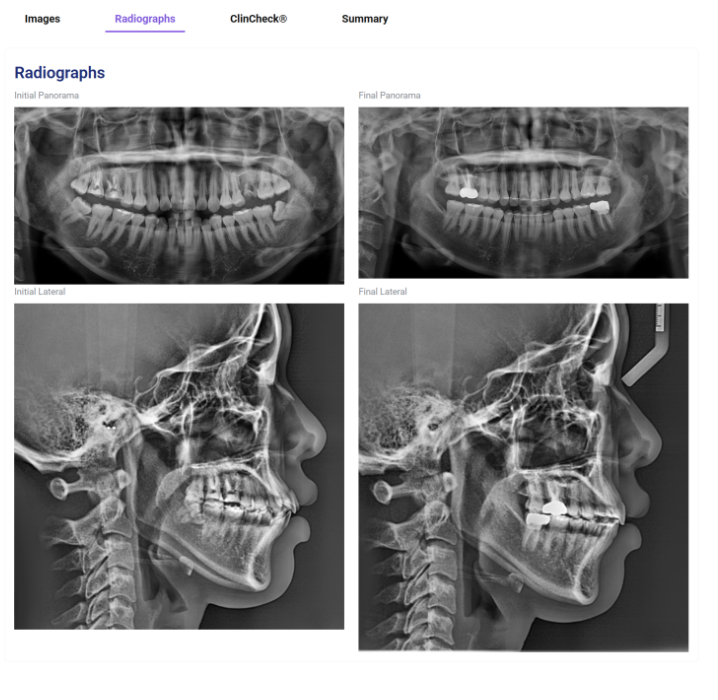

글로벌 갤러리에는 입안사진 뿐만 아니라 엑스레이도 함께 공개가 됩니다.

같은 맥락에서 저희가 증례 포스팅을 하면서 파노라마 엑스레이를 꼭 넣는 이유는

인비절라인 교정에서 치근흡수나 뿌리 정렬(치축 쓰러짐)에 대한 완성도와 안정성을 증명하기 위해서입니다.